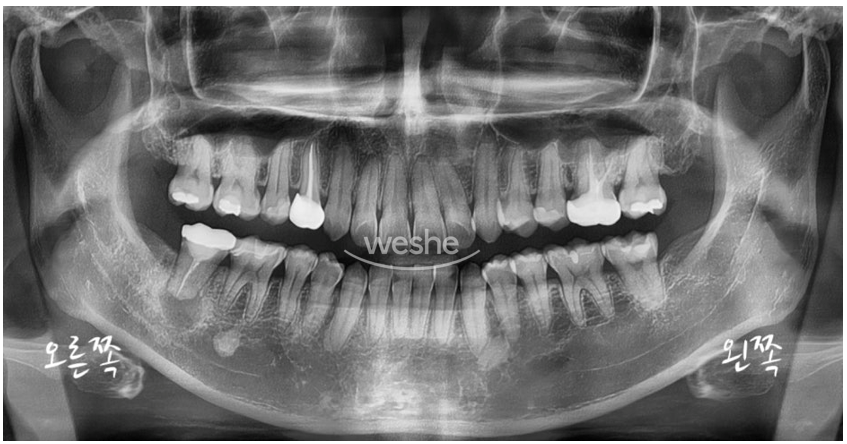

아래는 환자분의 파노라마 X-ray입니다.

생각하지 못한 문제가 발견되었습니다. 무엇일까요?

표시한 부위에 검은 음영이 관찰됩니다.

보통 건강한 치조골(잇몸뼈)은 X-ray 상에서 하얗고 회색빛의 결 구조가 나타나는데,

이처럼 어둡고 비어 보이는 음영은

염증 등으로 인해 뼈 조직이 약해졌거나 흡수되었을 가능성을 의미합니다.

해당 부위는 크기도 꽤 큰 편이어서,

더 정밀한 진단을 위해 CT 촬영을 진행하기로 했습니다.